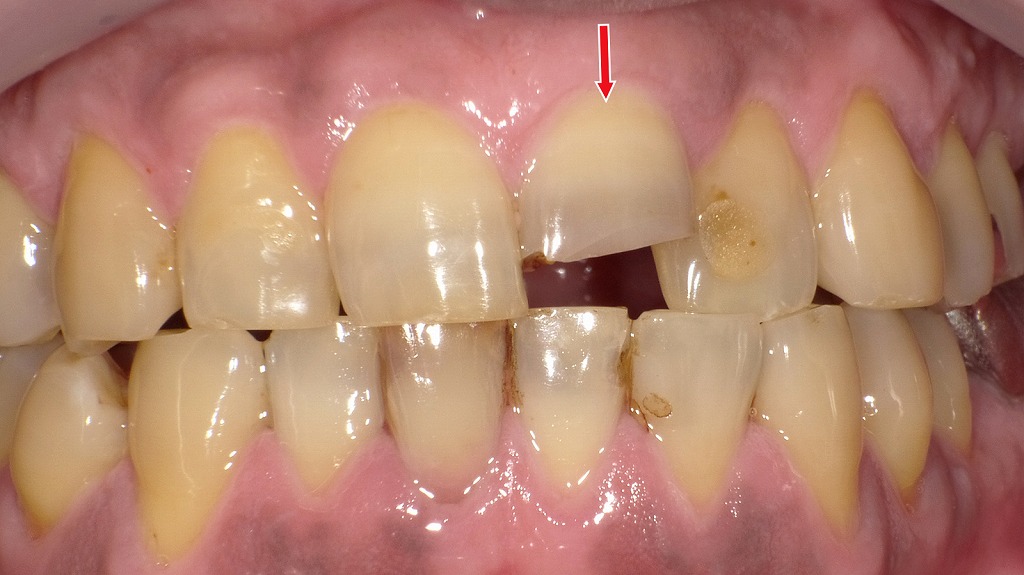

転倒や衝突などの外傷により、前歯の先端が欠けている状態です(矢印部)。歯が折れても痛みが少ない場合がありますが、内部の神経(歯髄)がダメージを受けていることもあり、放置すると変色や感染につながる可能性があります。外傷後は見た目に問題がなくても、早めに歯科での診察・レントゲン検査を受けることが大切です。